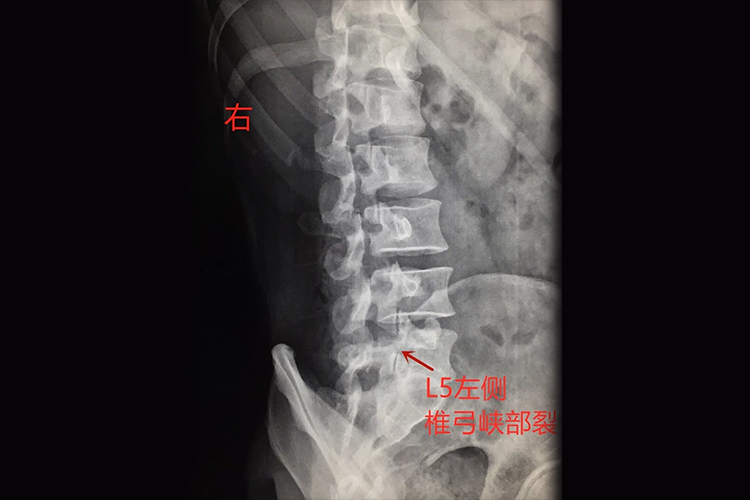

腰5椎弓峡部裂可通过X线平片进行诊断。正常椎弓附件呈“猎狗”形,当腰5椎弓峡部裂时,“狗颈”部可见一带状透亮裂隙。

腰5椎弓峡部裂是指椎弓峡部缺损不连,以下腰部出现进行性疼痛为主,可伴发单侧或双侧下肢放射性痛。通过X线平片检查可清楚显示腰5椎弓峡部裂隙。正常的斜位片投影,可以见到椎体附件形似猎狗,头为同侧横突,耳部为上关节突,颈部为峡部。当腰5椎弓峡部不连时,“狗颈”部呈现带状裂隙,俗称“狗脖子”戴项链或“项圈征”。